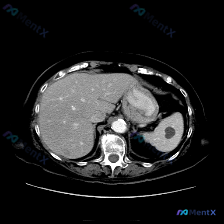

看到一份腹部CT的单幅影像分析,关于脾脏的这个病灶,觉得很有讨论价值,整理一下思路和大家分享。 --- 先看影像给出的客观发现 - 基本情况:单幅腹部CT横断面(层面未全,仅看所示范围) - 阳性表现: 1. 脾脏实质内见一类圆形低密度灶,边界尚清晰,内部密度均匀 2. 病灶CT值近似水样密度 3....

看到一张腹部CT的影像资料,焦点在脾脏,整理了一下读片和分析思路,分享给大家。 先看影像核心发现 这是一张上腹部CT横断面软组织窗: - 肝脏:实质密度基本正常,未见明确弥漫性病变或实性占位。 - 脾脏:形态明显失常,内部可见一个巨大的类圆形囊性占位,占据了脾脏大部分体积。 - 关键细节:病变内部是...

看到一份很有思辨意义的病例资料,整理了一下影像表现和分析思路,分享给大家。 病例核心信息 - 人群:男性患者 - 主诉/主要表现:全身症状(具体描述未细化,但作为核心就诊原因) - 关键影像:腹部CT平扫横断面 影像表现拆解 这张CT平扫的核心异常非常明确,在脾脏实质中部: 1. 典型形态:病灶核心...